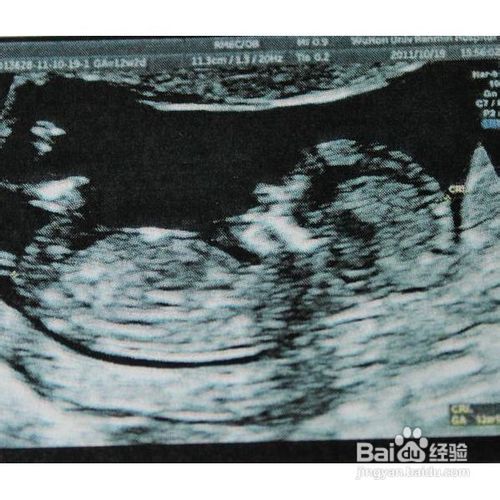

1、B型超声波检查。用B超诊断早孕是早孕诊断最正确可靠的方法。最早在妊娠第5周,亦就是月经过期一周,在B型超声波屏上就可显示出子宫内有圆形的光环,又称妊娠环,环内的暗区为羊水,其中还可见有节律的胎心搏动。